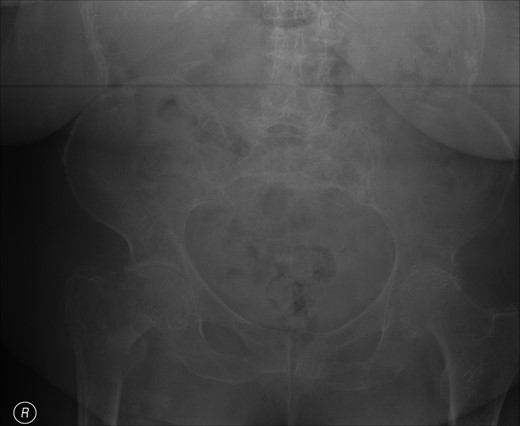

A lady of 88 years old presented with pain in her right hip following a fall at home. Radiographs of the proximal femur revealed an extra-capsular fracture, as shown in Fig. 1. She was taken to the operating theatre within 48 h. In an uncomplicated procedure, the fracture was fixed with a 75-mm, 135°, dynamic hip screw (DHS). A short (25-mm) barrel with four-hole plate was used. Intraoperative screening images are shown in Fig. 2. This position was accepted.

Review of the intraoperative radiographs (Fig. 2) shows that the barrel and screw are not properly engaged. Although the films may appear satisfactory at first glance, closer consideration reveals that the long axes of the barrel and screw are imperfectly aligned (Fig. 2). Following later experimentation on the bench with identical components, we discover that this is only possible when the length of overlap between barrel and screw is <3 mm. With such minimal overlap, the screw is resting on the lip of the barrel, yet is not fully engaged. In such a position, the screw cannot slide within the barrel. At overlaps greater than this, the screw and barrel cannot be other than coaxial.

Previous correspondents have explained the failure of the screw to slide within the barrel as a ratio of the length contained within the barrel, and the length protruding from it. In order to slide smoothly, without danger of binding, the length of screw protruding should be <4.7 times the length contained within the barrel [2]. This was not achieved here.

We hypothesize that the cause of failure was an intraoperative measurement error, leading to the selection and placement of a 75-mm screw, which was in fact of inadequate length. Thinking, however, that the selection was correct, the surgeon also chose to employ a short 25-mm DHS barrel following recommended practice from the literature [3]. This combination of components was too short to engage properly. Being improperly engaged, they were unable to slide as intended, and upon attempted mobilization by the patient, they immediately uncoupled the one from the other.

Intraoperative screening at the time of placement of the screw may concentrate on visualization of the proximal tip of the implant, to ensure that it occupies a satisfactory position in the femoral head and does not protrude into the hip joint. We stress that equal attention should be paid to the distal end, to ensure that it is correctly aligned with the barrel. Closer scrutiny of the intraoperative screening films for evidence of the appearance described above could have identified this avoidable complication, the resolution of which required major revision surgery.